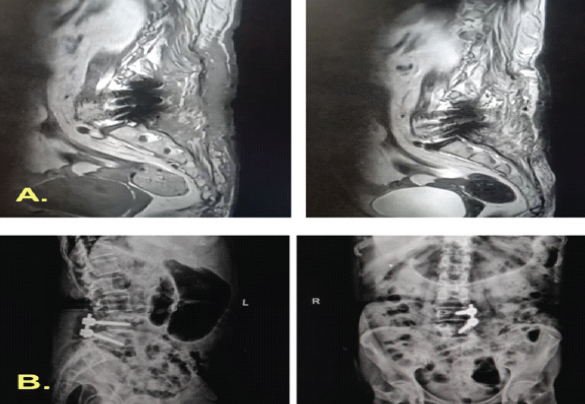

However, by 2.5-month post-index surgery, clear fluid discharge persisted, indicating a refractory CSF leak. A thecoperitoneal shunt was inserted, after which she was discharged. Two months later (4 months from the index procedure), she presented with meningitis and recurrent CSF leakage, suggesting shunt failure. Intrathecal colistin and temporary Mini Vac drainage were administered. Ultimately, 2 months after shunt placement, it was removed, and a primary dural repair was performed under general anesthesia (Fig. 5).

Figure 5: Post-operative imaging following fifth debridement and definitive repair. Magnetic resonance imaging and radiographs obtained immediately after the fifth debridement and re-exploration demonstrate removal of the thecoperitoneal shunt and right-sided pedicle screws, with evidence of successful cerebrospinal-fluid leak repair and resolution of the collection.